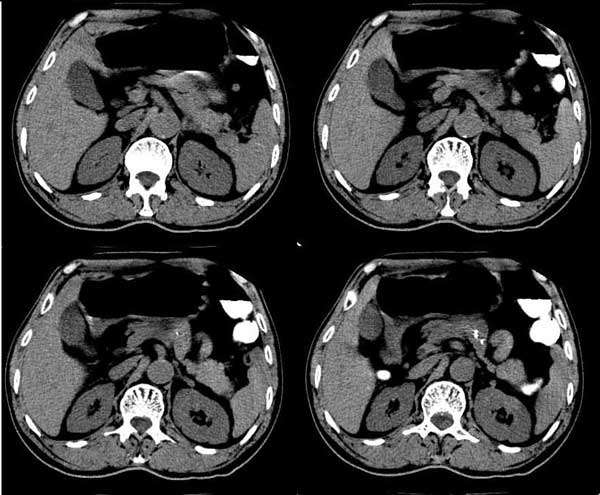

m/76 患者于2个多月前无明显诱因出现解肉眼血尿,为淡暗红色,无尿急、尿痛、脓尿,自服中草药后症状缓解

膀胱内高密度ct值约62hu

膀胱内偏右后方附壁见不规则软组织密度块影,边缘有分叶,综合患者症状考虑膀胱癌。

本人首先考虑膀胱内血凝块!跟踪临床经膀胱镜检查证实,但另有发现:膀胱冲洗血凝块后发现右侧壁见菜花样物质。

患者行膀胱镜检查,将血块冲洗后发现有菜花样物质! 当时完全被血块掩盖了!

今天下午病理出来了,是膀胱移行细胞癌